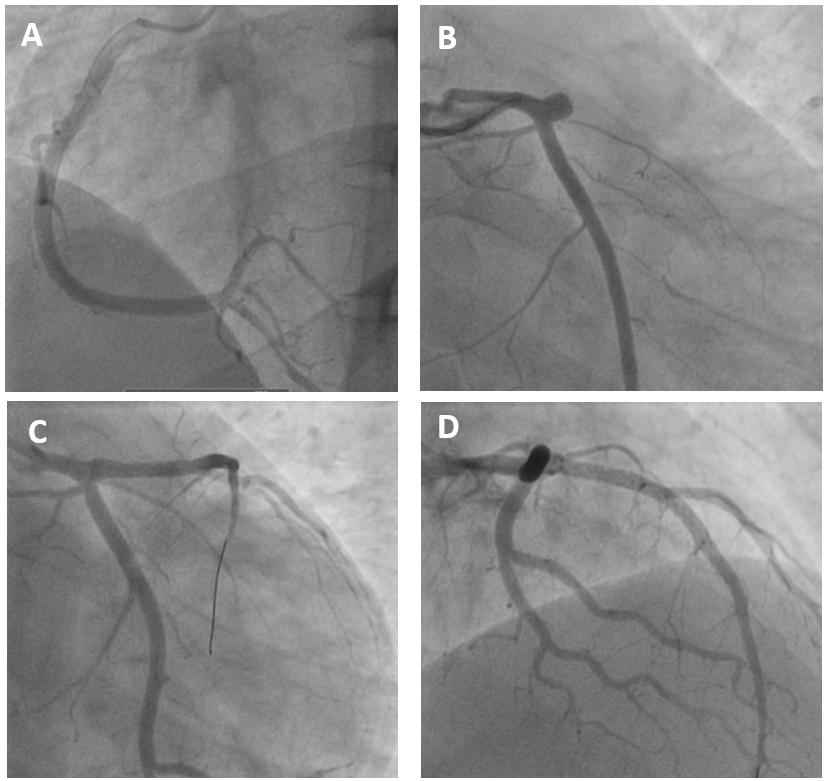

Procedural Step

Primary percutaneous coronaryintervention (PPCI) was performed via right radial artery access. A 6 Fr Tigercatheter was used for diagnostic angiography, followed by a 6 Fr XB 3.5 guidingcatheter for intervention. The LAD lesion was crossed with a floppy guidewireand pre-dilated using a semi-compliant balloon. Two drug-eluting stents (DES)were implanted: 3.5 ¡¿ 20 mm in the proximal LAD and 3.0 ¡¿ 30 mm in the mid LAD.Post-dilatation was performed to optimize stent expansion and apposition. Finalangiography showed TIMI 3 flow with no residual stenosis or dissection. Thepatient was started on dual antiplatelet therapy (aspirin and ticagrelor),statins, and beta-blockers. Recovery was uneventful, and he was discharged instable condition.